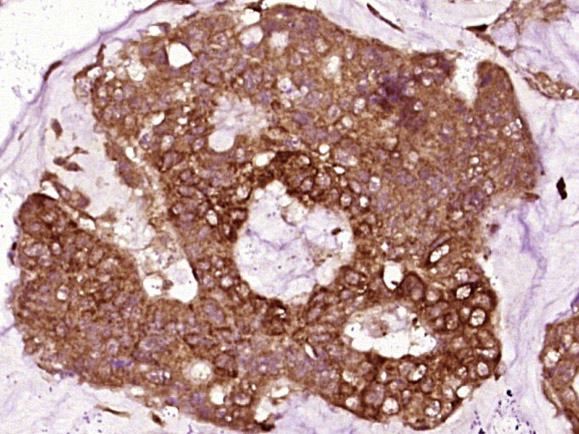

Antigen retrieval: citrate buffer ( 0.01M, pH 6.0 ), Boiling bathing for 15min; Block endogenous peroxidase by 3% Hydrogen peroxide for 30min; Blocking buffer (normal goat serum,C-0005) at 37℃ for 20 min;

Incubation: Anti-Vinculin Polyclonal Antibody, Unconjugated(bs-6640R) 1:200, overnight at 4°C, followed by conjugation to the secondary antibody(SP-0023) and DAB(C-0010) staining